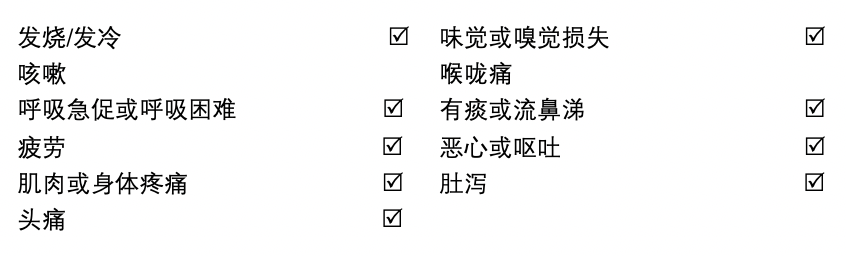

以下是在接触新冠患者2-14天后会出现的症状,但我没有咳嗽或喉咙痛。那究竟该如何判断自己是普通感冒,还是得了新冠呢?

一般来说,新冠一开始会体温偏高及低烧,然后才会慢慢出现咳嗽鼻塞等症状,在这之前你都有可能只是普通的感冒。要是出现持续的肌肉疼痛,疲劳及恶心的话,那就要开始注意了。

新冠最大的特点是突然失去味觉嗅觉!

我觉得新冠最令人头疼的就是一直反反复复,每天早上精神比较好,傍晚开始浑身疲惫,突然没了嗅觉和味觉,肌肉酸痛,骨痛及肚泻也偶尔出现,有时候还有感冒的感觉。呼吸要深呼吸才会比较舒服,间中呼吸会感到胸口有轻微的疼痛。